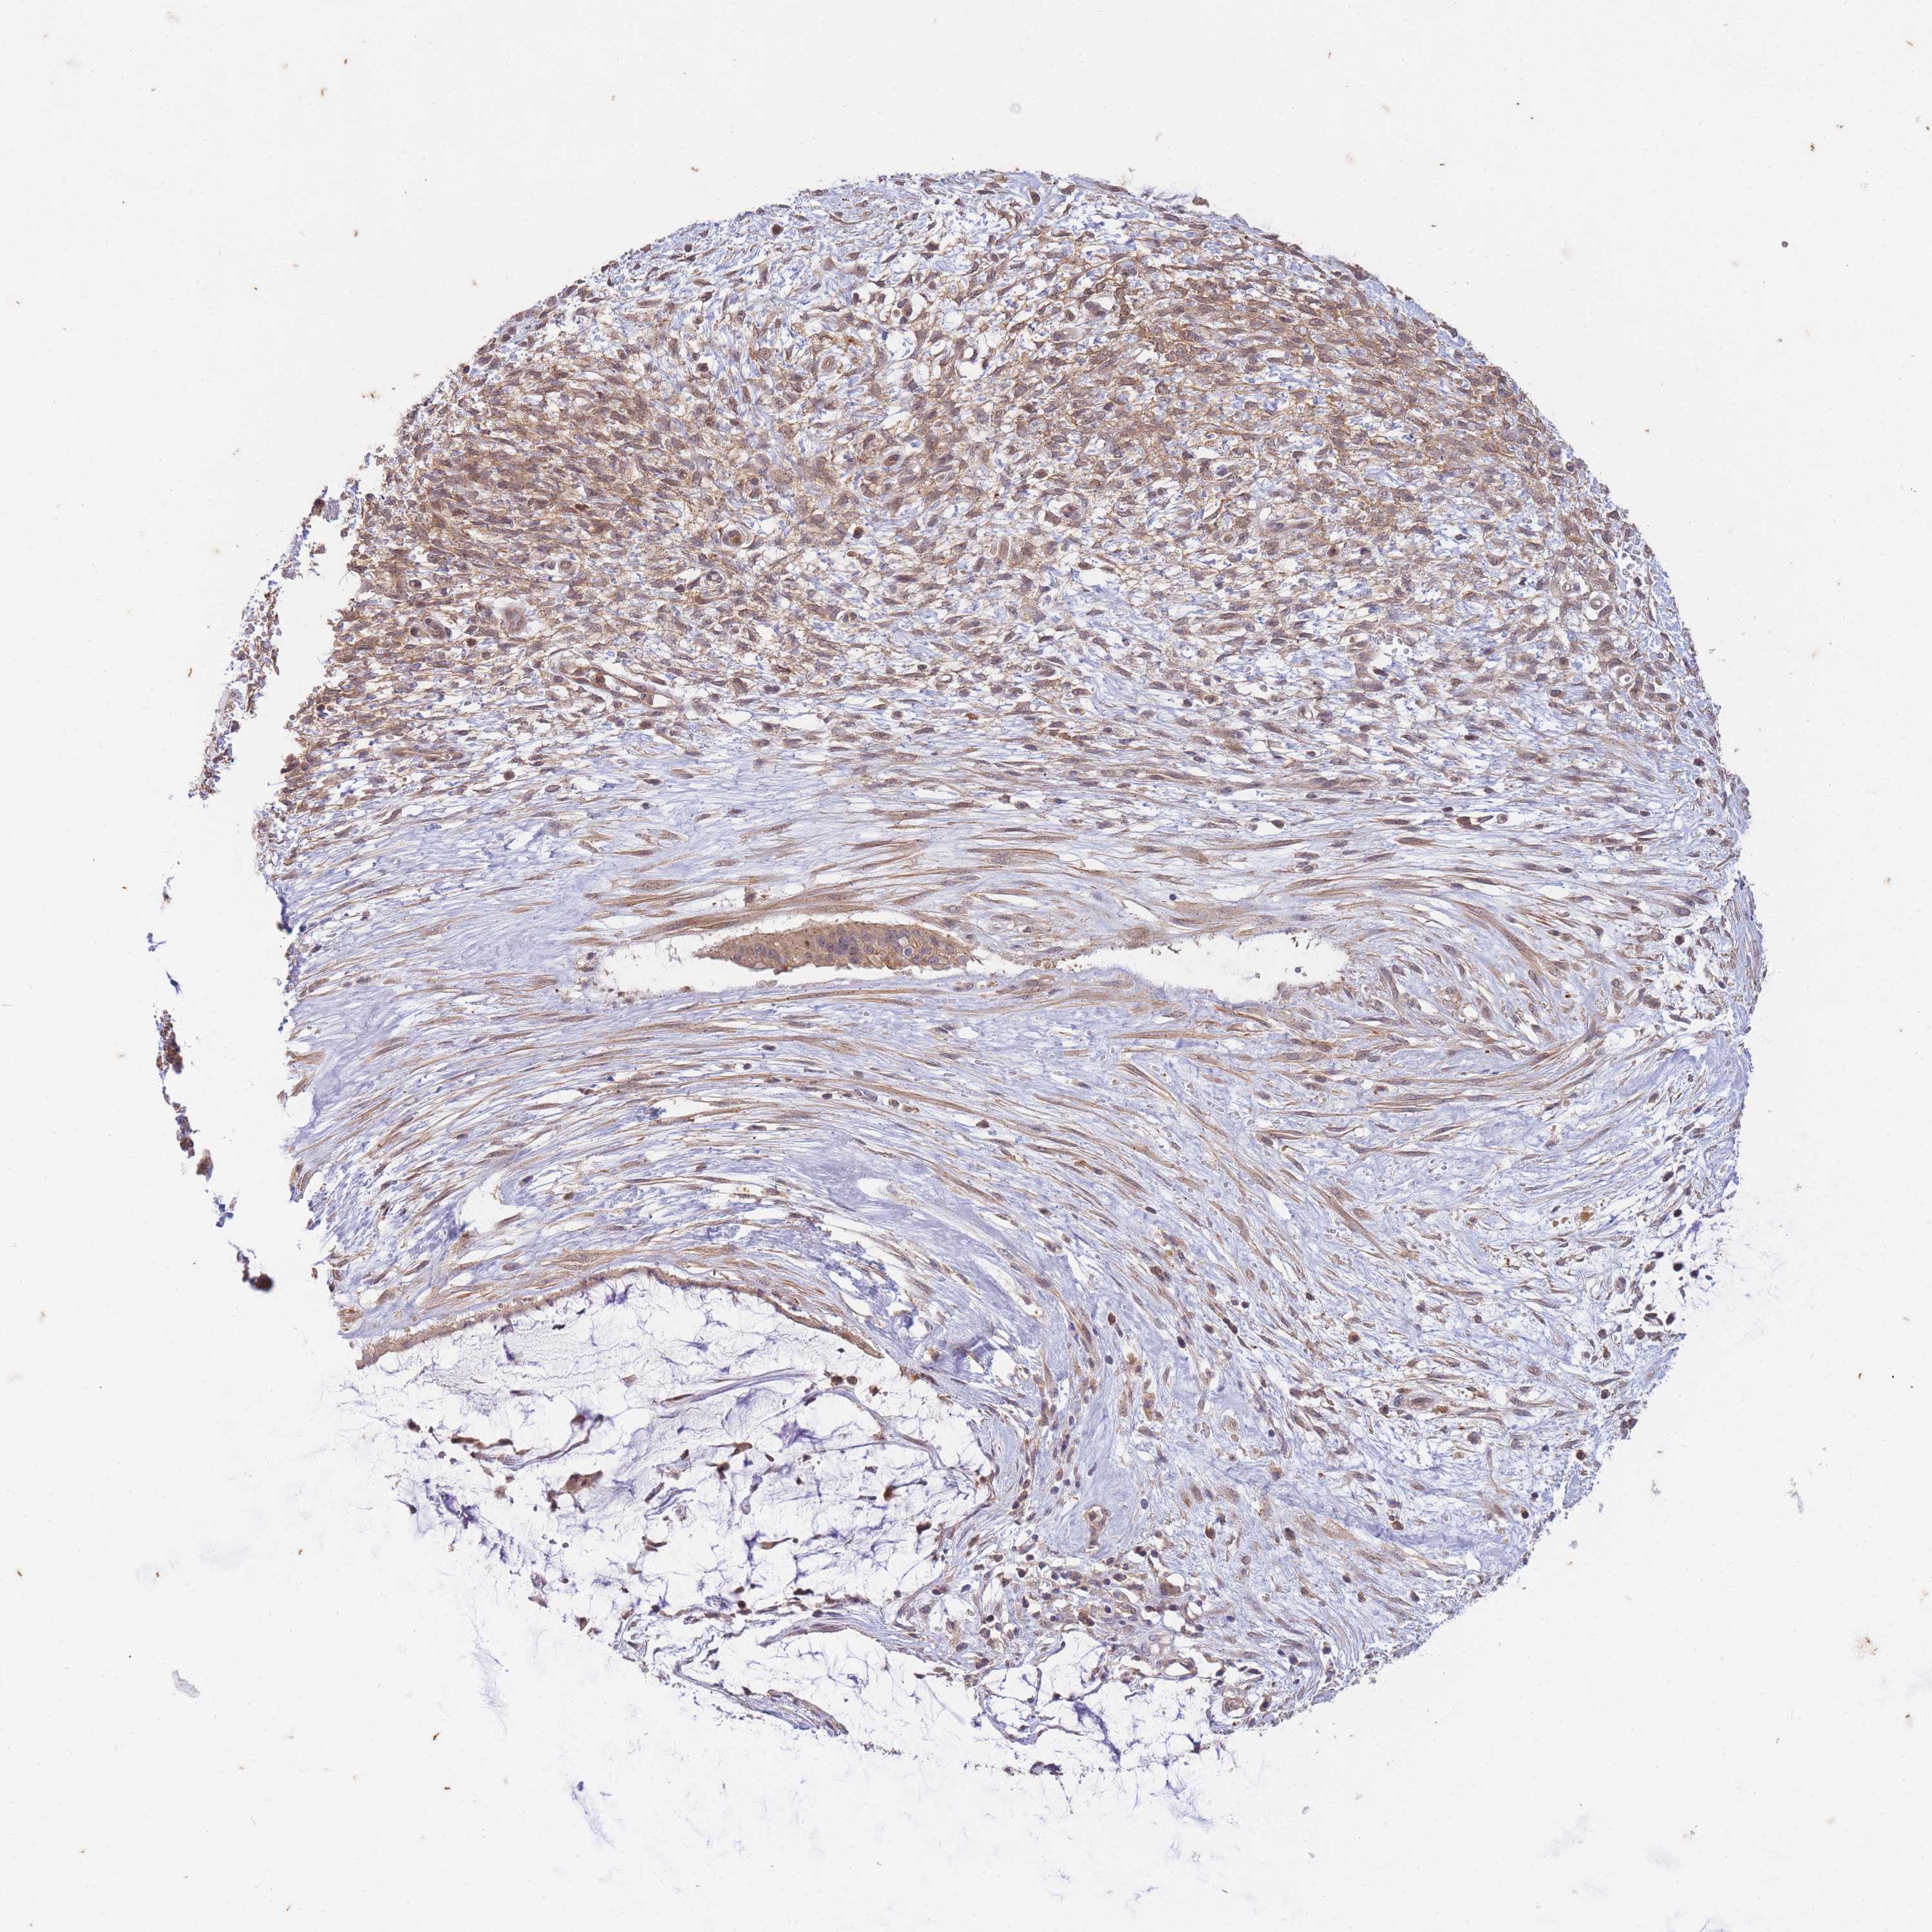

OVARIAN CANCER - Protein expressioni

A mouse-over function shows sample information and annotation data. Click on an image to view it in a full screen mode. Samples can be filtered based on level of antibody staining by selecting one or several of the following categories: high, medium, low and not detected. The assay and annotation is described here.

Note that samples used for immunohistochemistry by the Human Protein Atlas do not correspond to samples in the TCGA dataset.

Antibody stainingi

Antibody staining in the annotated cell types in the current human tissue is reported as not detected, low, medium, or high, based on conventional immunohistochemistry profiling in selected tissues. This score is based on the combination of the staining intensity and fraction of stained cells.

Each image is clickable and will lead to virtual microscopy that enables deeper exploration of all samples and also displays staining intensity scores, fraction scores and subcellular localization as well as patient and tissue information for each sample.

Antibody HPA051126

Staining

High

Medium

Low

Not detected

Intensity

Strong

Moderate

Weak

Negative

Quantity

>75%

75%-25%

<25%

None

Location

Nuclear

Cytoplasmic/membranous

Cytoplasmic/membranous,nuclear

Cystadenocarcinoma, serous, NOS

Carcinoma, NOS

Cystadenocarcinoma, mucinous, NOS

Carcinoma, endometroid